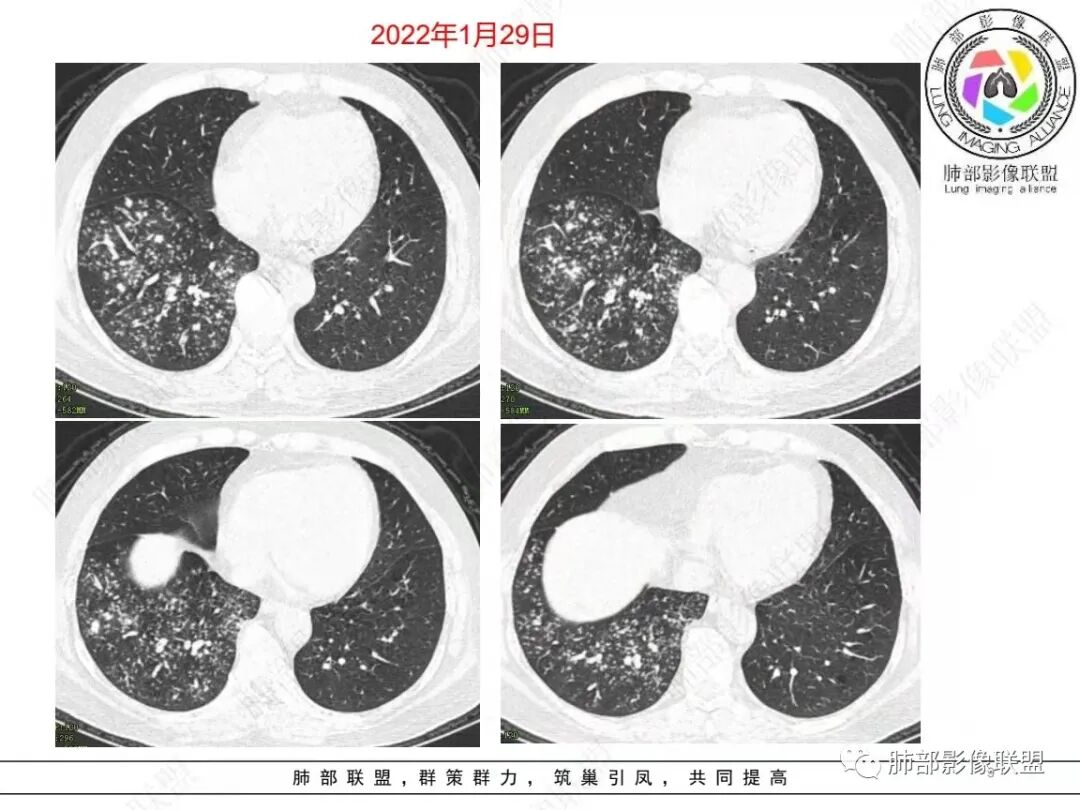

右肺下叶多发腺泡结节影,边缘部分模糊,伴树芽征,支气管壁增厚,10天复查腺泡结节有吸收变淡,病变内出现多发囊状影,考虑感染性病变,金葡?真菌?

右肺下叶多发腺泡结节影及树芽征,抗炎治疗后吸收好转,白细胞及中性明显增高,有糖尿病病史,首先考虑气道来源感染性病变,金葡菌?吸入?

中年男性,咳嗽咳黄脓痰一周,有糖尿病,肾病病史,长期使用激素血象白细胞自然会升高,但CRP明显升高。降钙素原不高,肺泡灌洗液阴性。右下肺沿支气管分布腺泡结节影,少于树芽征,小实变影,支气管壁轻度增厚,考虑感染性疾病,从病灶形态来看气道来源,复查病灶有小空洞形成,病灶明显吸收。考虑气道金葡菌肺炎,鉴别奴卡菌

中老年 男性 白细胞高,基础病多, 右肺下叶多发小结节 小斑片影,边缘模糊,伴树芽征,支气管壁略增厚,短期治疗后复查病灶有所吸收,可见小囊状透光区形成,考虑气道来源化脓性感染,金葡 可能

中老年男性,糖尿病史,免疫抑制,白细胞及C反应蛋白明显升高,右肺下叶多发腺泡结节、树芽,边缘模糊,支气管管壁增厚,治疗10日复查吸收好转,可见小空洞,考虑金葡,鉴别曲霉

57岁男性,糖尿病、肾病基础。白细胞升高、以中性升高为主,黄浓痰提示细菌感染、球菌可能大。结核几次相关检查都阴性,可能性不大。几次血培养无细菌生长,结合影像,病灶不是血播而是气道播散。影像:沿气道播散,树芽明显,(树芽有没有特征?部分枝细芽大?),部分支气管弥漫增厚,治疗10后复查,临床没有怀疑真菌类,结核阴性,所以抗结核抗真菌的可能小,只能是抗炎治疗10天后复查,树芽缩小、部分消散,支气管壁变薄,提示抗菌有效,但部分出现了气囊空洞。细菌、空洞、黄浓痰,加起来,首先考虑金葡菌支气管播撒应该顺理成章。

南边:急性、慢性,看树芽征的边缘。NTM也好,结核也好,他们属于慢性病变、反复发作,毒力不那么强,所以他相对来说发展速度非常慢,病变以增殖为主,因此他的边缘比较清楚,也可以引起支气管增厚。但是金葡菌是急性感染,所以他的边界是非常模糊的,外围磨玻璃非常多。

病变区支气管壁弥漫增厚,远端树芽征,周围GGO——渗出

4.金葡——小气道、肺泡,早期小叶性肺炎:树芽征、腺泡结节等

小气道树芽征、周围渗出——GGO